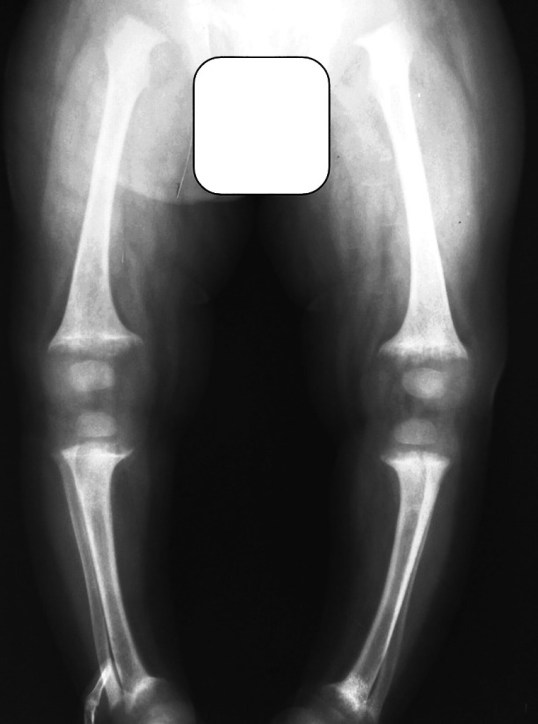

d. Due to soft bones, there are acquired skeletal deformities like bow legs and knock knees (see case below).

5. Residual deformities such as knock knees and bow legs remain. These skeletal deformities may be confused for skeletal dysplasias at the first instance. For example, a boy who has had healed rickets in early childhood is often diagnosed with Blount’s disease by the paediatrician, statistically this is going to be healed old rickets in almost all cases.